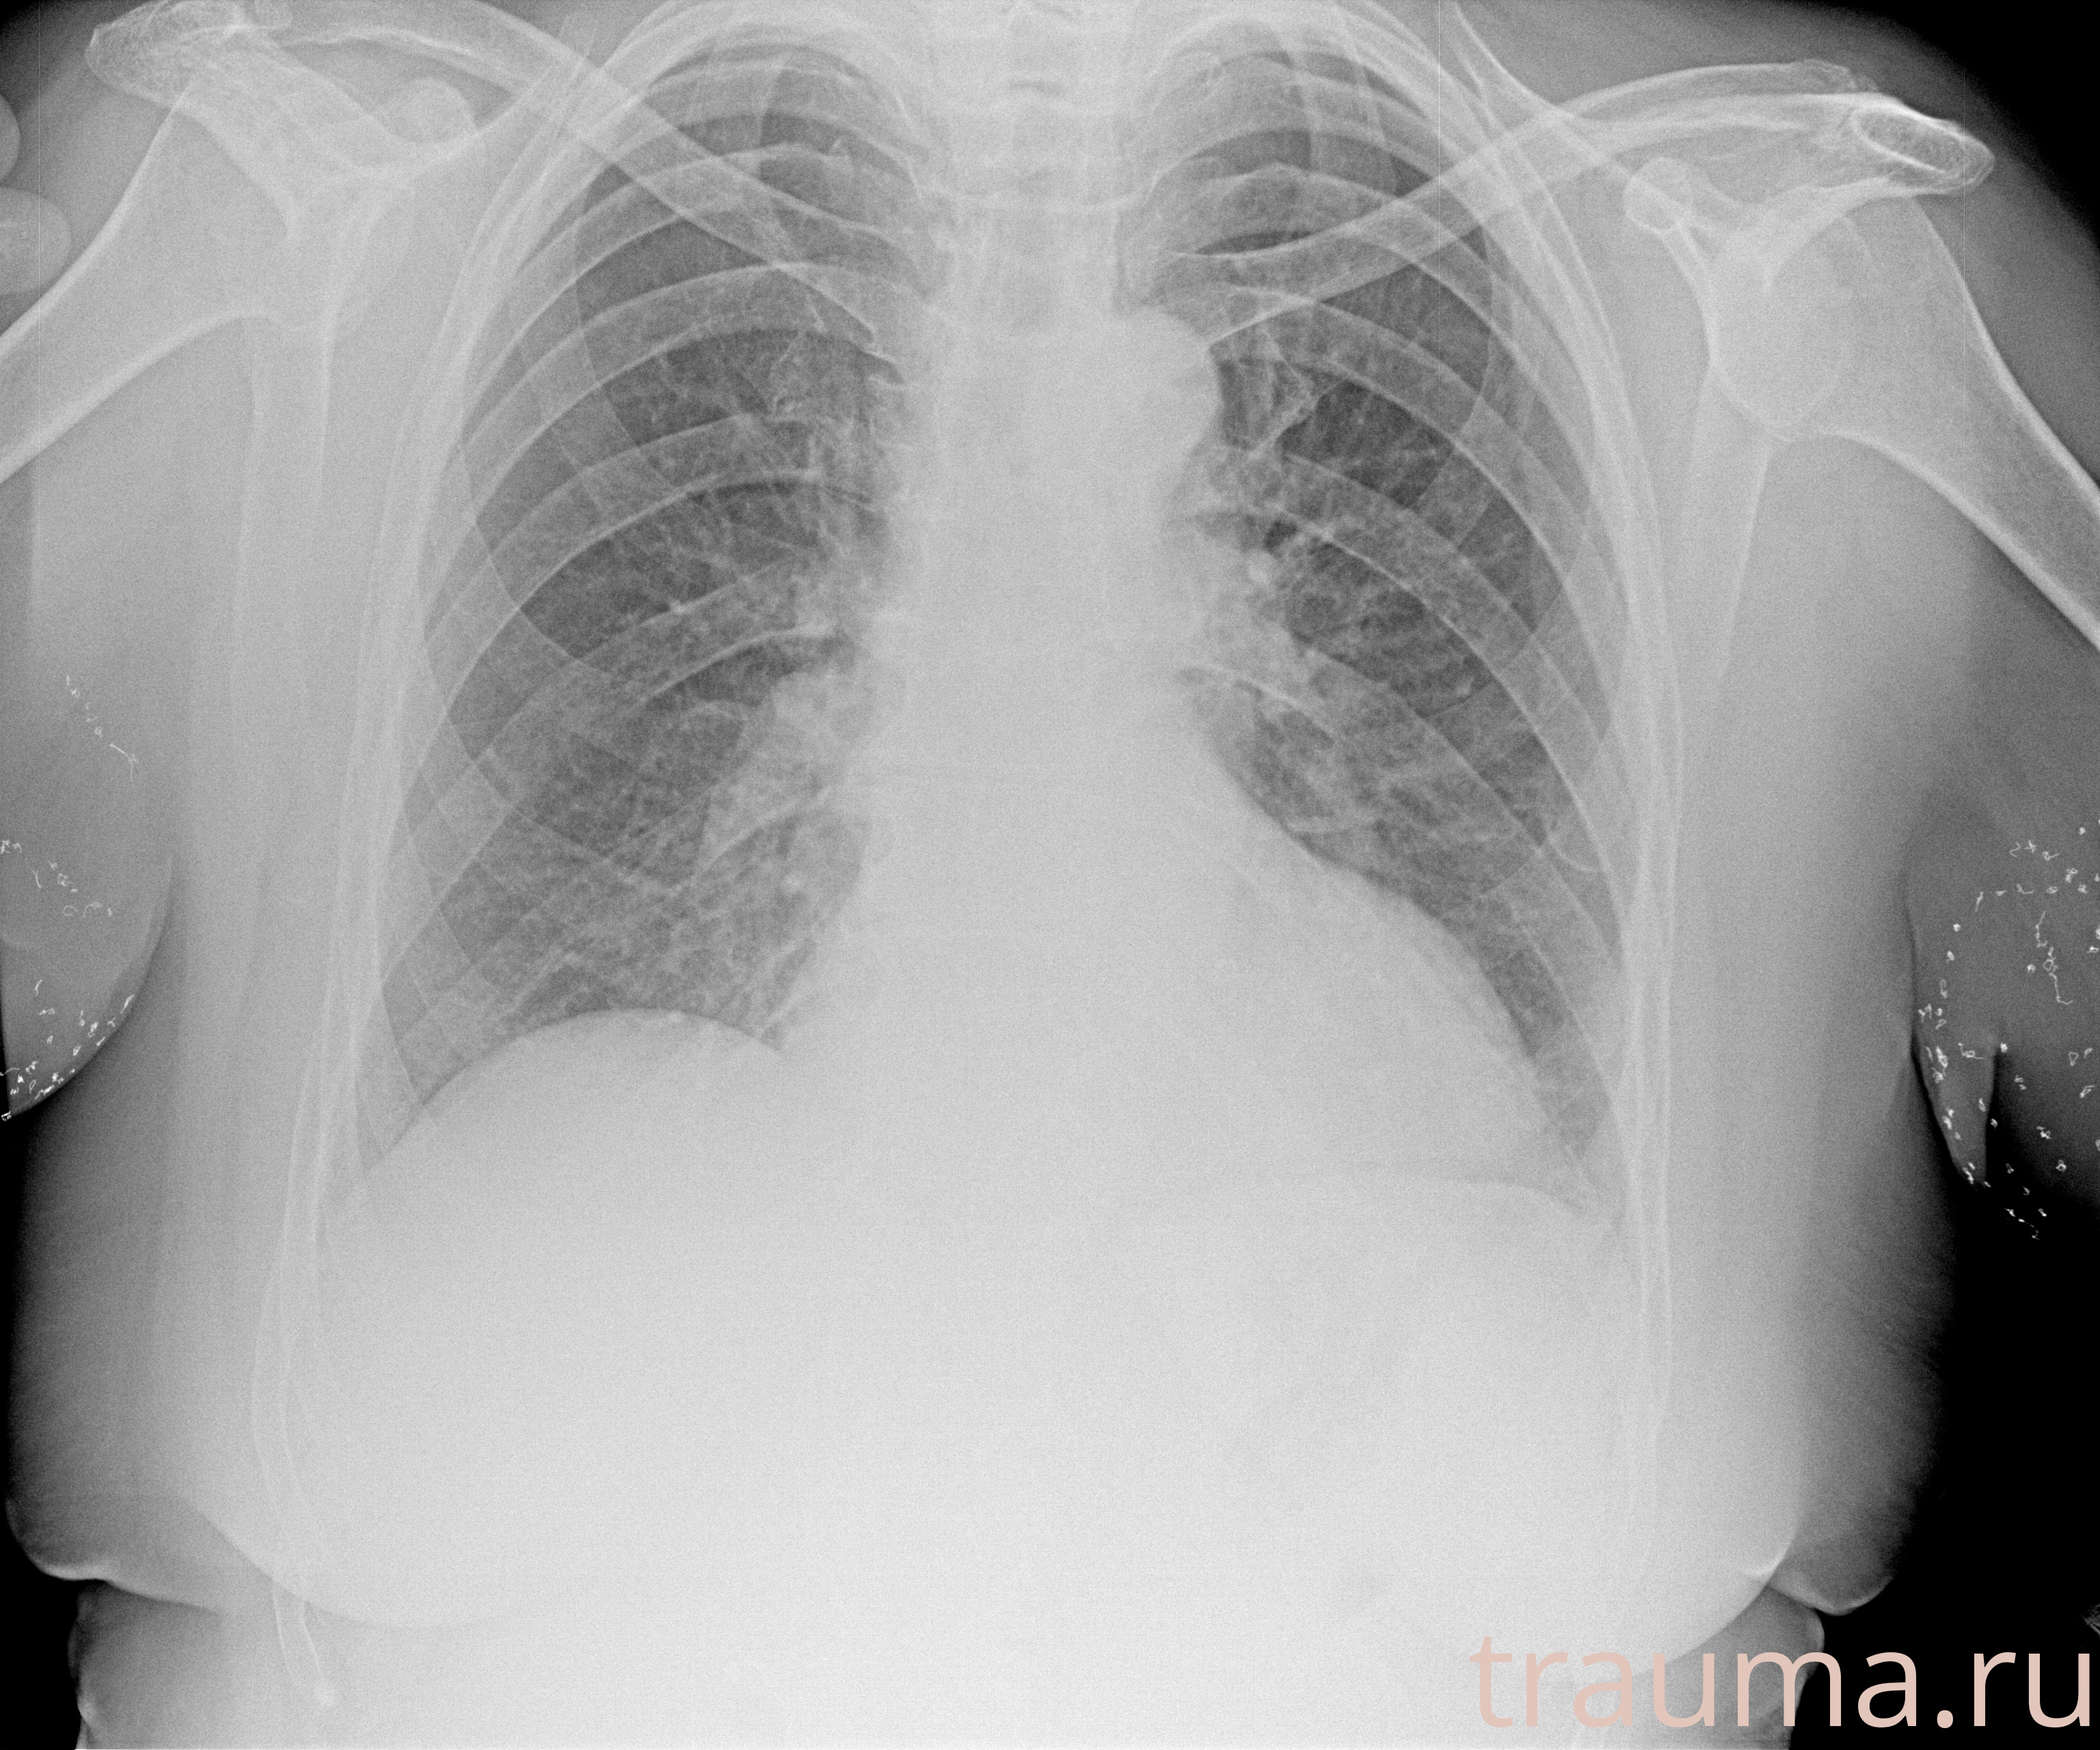

Рентген на дому: по вашему адресу приезжает врач-рентгенолог, травматолог-ортопед с мобильным рентгеновским аппаратом, проводит диагностику травмы или заболевания, делает необходимые рентгенограммы, дает рекомендации по дальнейшему лечению. Получить качественные снимки в домашних условиях возможно благодаря уникальной методике, разработанной МосРентген Центром для института  Склифосовского

при переломе шейки бедра и пневмонии от компании МосРентген Центр - партнера Института имени Склифосовского